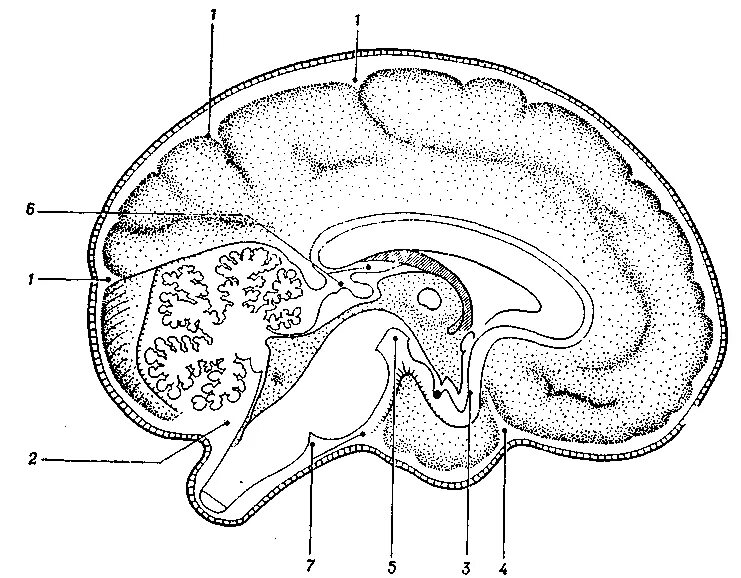

Цистерны на кт